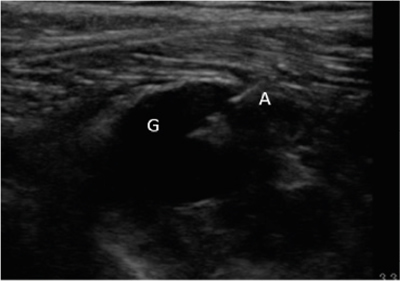

Figura 1

Figura 2